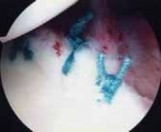

The foundation of a successful arthroscopic stabilization is the meticulous mobilization of the capsulolabral complex. In chronic cases, the torn labrum and IGHL frequently heal in a medially displaced position along the anterior glenoid neck (the ALPSA lesion). Using a combination of arthroscopic elevators, rasps, and electrocautery, the surgeon must aggressively liberate this tissue from the scapular neck. The release must extend inferiorly to the 6 o'clock position to adequately mobilize the inferior capsule. Once the tissue is freed and can be easily reduced to the articular margin, the anterior glenoid neck is lightly decorticated using a motorized burr or rasp. This critical step removes fibrous tissue and exposes bleeding cancellous bone, creating an optimal biological environment for robust soft-tissue healing.